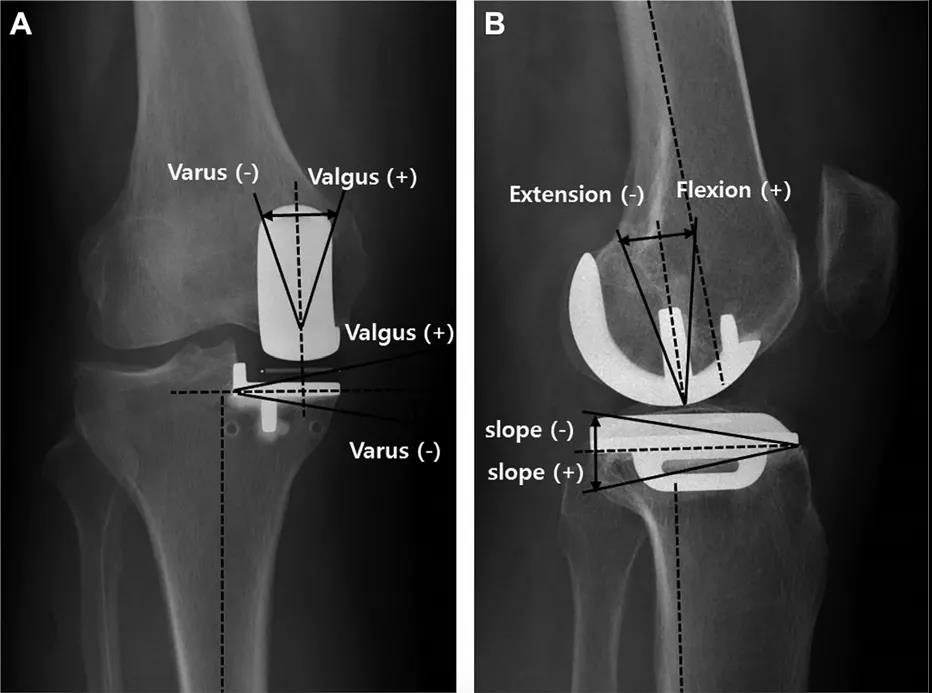

影像学指标

研究者回顾了来自单一中心共253例初次固定平台和活动平台单髁置换手术。所有手术由两名高手术量经正规培训的关节外科医生完成。在他们每年的外科实践中,单髁手术的比例不足10%,平均每人每年行14.2例内侧单髁置换手术。最终我们统计了假体生存率。评价指标包括股骨冠状面成角(FCA),股骨矢状面成角(FSA),胫骨冠状面成角(TCA),胫骨矢状面成角(TSA)和假体悬出。异常值被定义为FCA(偏离中立位±10°以上),FSA(屈曲大于15°),TCA(偏离中立位±5°以上)和TSA(偏离7°后倾±5°以上)。极端异常值被定义为异常值基础上再偏离±2°以上。悬出被定义为前方悬出超过3mm,后方悬出超过2mm,内侧悬出超过2mm。

Methods: We performed a retrospective analysis of 253 primary fixed-bearing and mobile-bearing medial UKAs from a single academic center. All UKAs were performed by 2 high-volume fellowship-trained arthroplasty surgeons. UKAs comprised<10% of their knee arthroplasty practices, with an average of 14.2 medial UKAs per surgeon per year. Implant survival was assessed. Femoral coronal (FCA), femoral sagittal (FSA), tibial coronal (TCA), and tibial sagittal (TSA) angles as well as implant overhang were radio graphically measured. Outliers were defined for FCA (>±10° deviation from neutral),FSA (>15° of flexion),TCA (>±5° deviation from neutral), and TSA (>±5° deviation from 7°). “Far outliers” were an additional >±2° of deviation. Outliers for overhang were identified as >3 mm for anterior overhang, >2 mm for posterior overhang, and >2 mm for medial overhang.